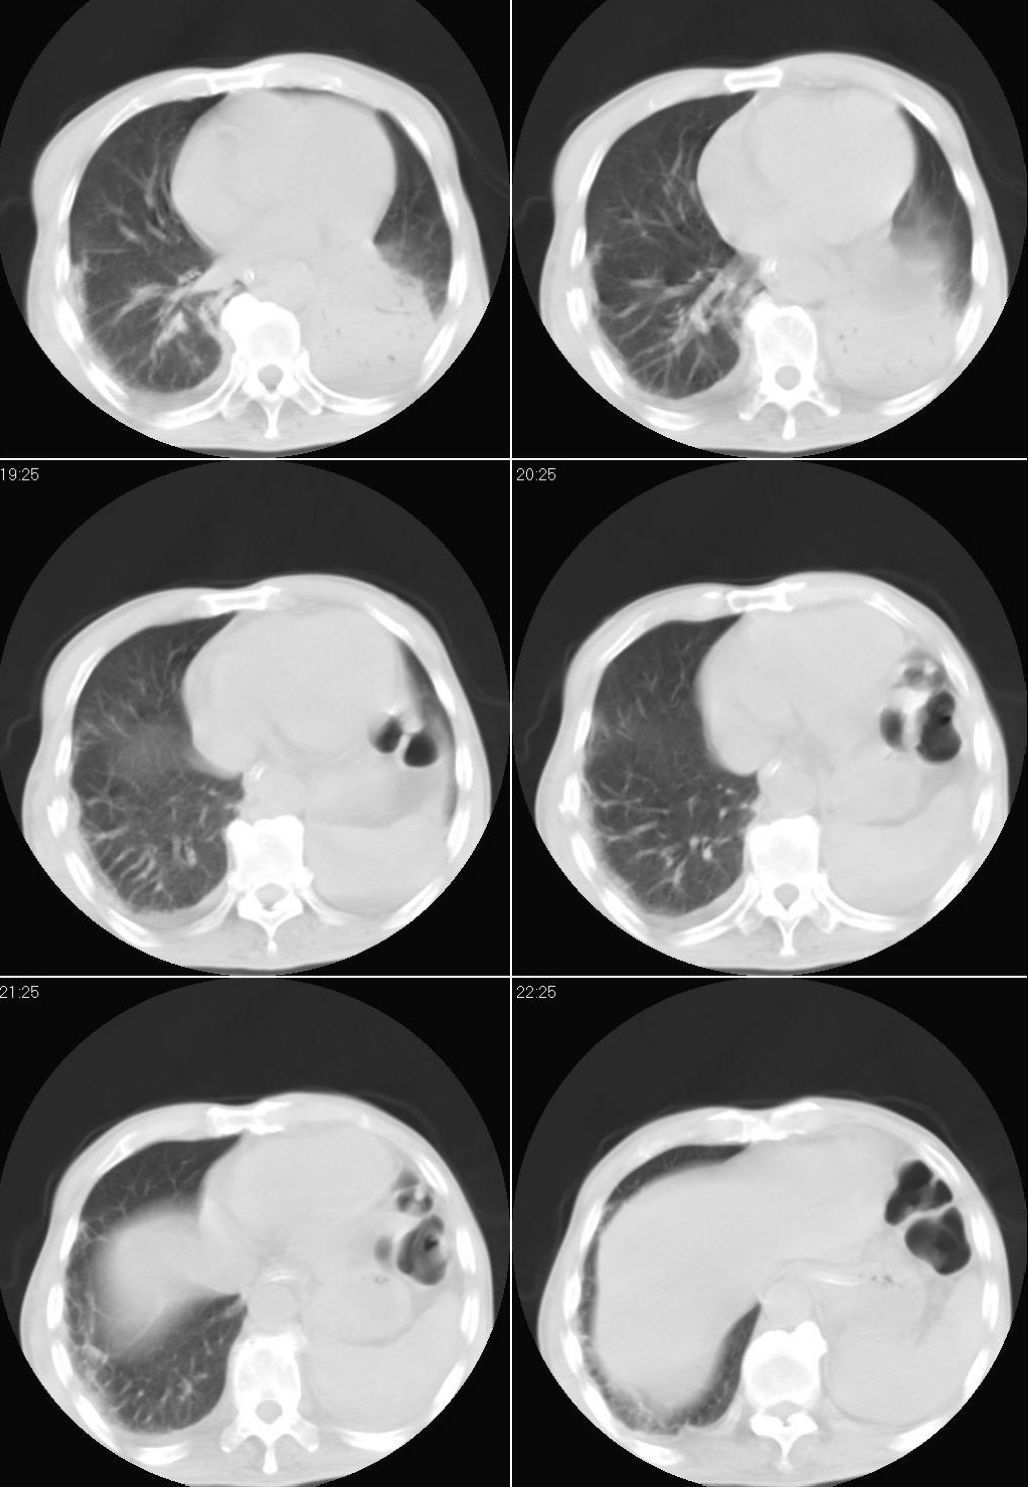

男性,65岁。因外伤来诊。该患者因脑外伤住院。以下是今天的dr和ct:

一周前胸片无异常,不考虑肿瘤,现x片及ct表现应与外伤有关,考虑左侧外伤性膈疝,并左下肺不张。右肺挫裂伤。少量胸水。

一周前胸片无异常,不考虑肿瘤,现x片及ct表现应与外伤有关,考虑左侧外伤性膈疝,并左下肺不张。右肺挫裂伤。少量胸水。支持

1 外伤性左侧膈疝、胸腔积液致左肺下叶不张 2右肺挫伤

右侧第7肋骨腋段骨折并右肺挫伤;左侧膈疝并肺不张。